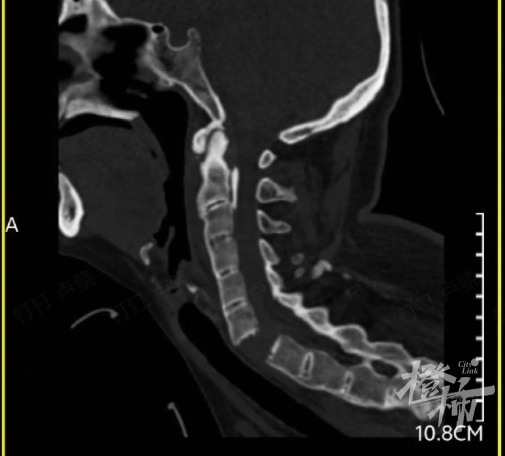

当时,刘女士出现颈部疼痛、四肢无力的症状,紧接着发现自己全身不能活动。随后,她被紧急送往附近的医院救治。通过颈椎影像检查后发现,刘女士颈椎6-7节完全断离,颈椎骨折造成脊髓损伤,导致全身瘫痪。

▲检查发现,刘女士的颈椎完全断离。